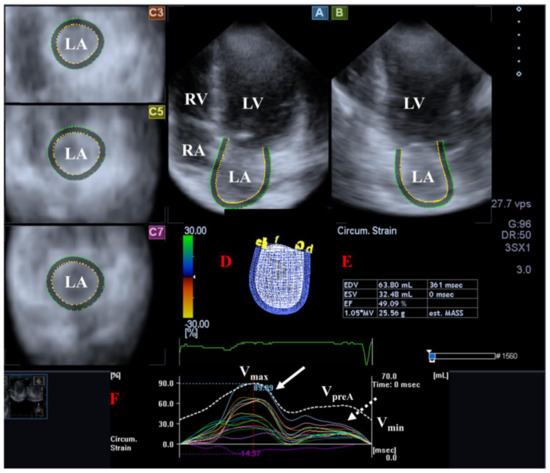

The LV is the central engine of systemic circulation. The two papillary muscles of the LV are required for the proper function of the mitral valve (MV) separating the LV and the left atrium (LA) and allowing blood flow from the LA into the LV during diastole. The blood leaves the LV via the aortic valve (AV), which prevents the backflow of blood from the aorta to the LV during diastole under healthy circumstances. The fibers in the subepicardium are left-handed, the mid-layer fibers run in the circumferential direction, while the fibers in the subendocardium are right-handed [16]. The LV moves in a 3D pattern including radial, circumferential and longitudinal deformation. This sort of movement can be characterized by several quantitative parameters named echocardiographic (unidirectional strains represented by its 3D motion: radial (LV-RS), longitudinal (LV-LS) and circumferential (LV-CS). While area (LV-AS) strain combines LS and CS, 3D (LV-3DS) strain combines all unidirectional strains [5,6,7,8,17,18,19,20]. In addition to the above, LV has a movement similar to wringing a towel called LV twist. In this case, the LV base rotates in a clockwise direction, while the LV apex rotates in a counterclockwise direction in systole [17,18,19] [Figure 1].

Figure 1.

Examination of the left ventricle (LV) by three-dimensional (3D) speckle-tracking echocardiography. Following echocardiographic data acquisitions, the following typical views are created: (A) Apical 4-chamber and (B) two-chamber longitudinal views and (C3,C5,C7) cross-sectional views at apical, midventricular and basal levels, respectively. LV can be easily detected alongside other heart cavities including the left atrium (LA) and the right atrium (RA) and ventricle (RV). A number of other details were also presented including (D) 3D cast and (E) end-diastolic (EDV) and end-systolic (ESV) volumes of the LV together with ejection fraction (EF) and mass of the LV and (F) curves representing changes in volumes and strains of LV over time. (F) Apical [white arrow] and basal [white dashed arrow] LV rotations and (G) radial, (H) longitudinal, (I) circumferential, (J) area and (K) 3D strains are also demonstrated.